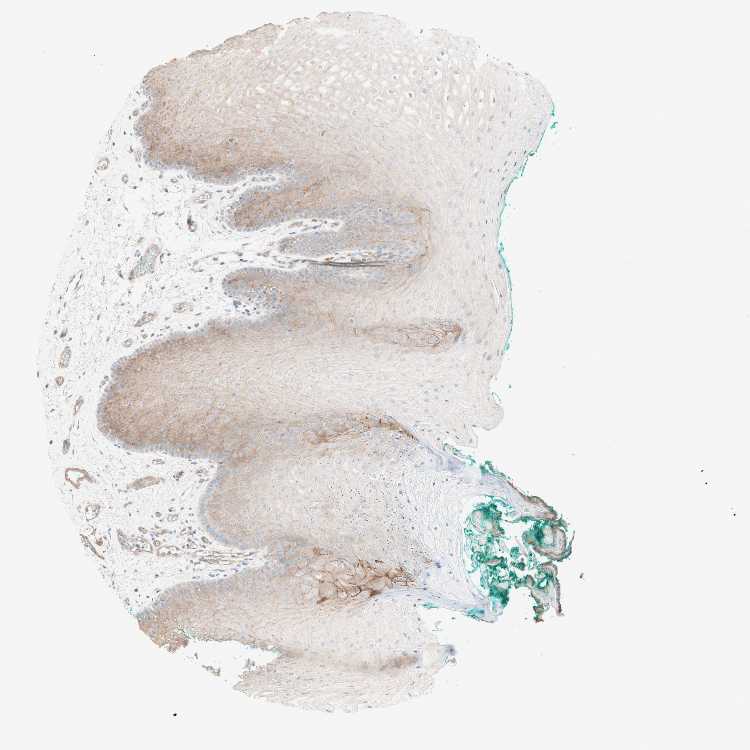

TISSUE PRIMARY DATA ORAL MUCOSA Show tissue menu

ORAL MUCOSA - Antibody stainingi

Antibody staining in the annotated cell types in the current human tissue is reported as not detected, low, medium, or high, based on conventional immunohistochemistry profiling in selected tissues. This score is based on the combination of the staining intensity and fraction of stained cells.

Each image is clickable and will lead to virtual microscopy that enables deeper exploration of all samples and also displays staining intensity scores, fraction scores and subcellular localization as well as patient and tissue information for each sample.

Antibody HPA001813Antibody CAB009228

Squamous epithelial cells MediumLow